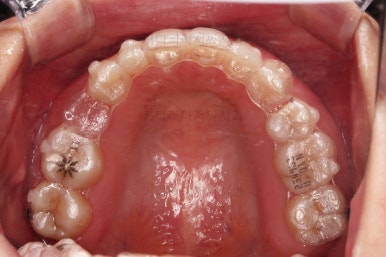

초진 시 입안의 모습인데요.

왜 그런지 비밀이 풀리는 것 같죠?

윗니는 한 쪽이 치아 2개가 결손이면서 유치가 하나 남아있고요.

아랫니는 한 쪽은 1개, 반대편은 2개 치아가 결손이었습니다.

도합 5개의 치아가 결손이었는데요.

결손 위치의 갯수가 위아래 좌우 다 달라서 중앙선이 맞을래야 맞을 수가 없는 상황이었죠.

결손치아 주위 치아들은 쓰러지고 비틀어져 있어서 장기적으로 좋지 못한 상황이었고요.

좀 더 디테일하게 윗니 작은 앞니 1개가 왜소치아라서 치아 크기도 맞지 않은 상황이었습니다.